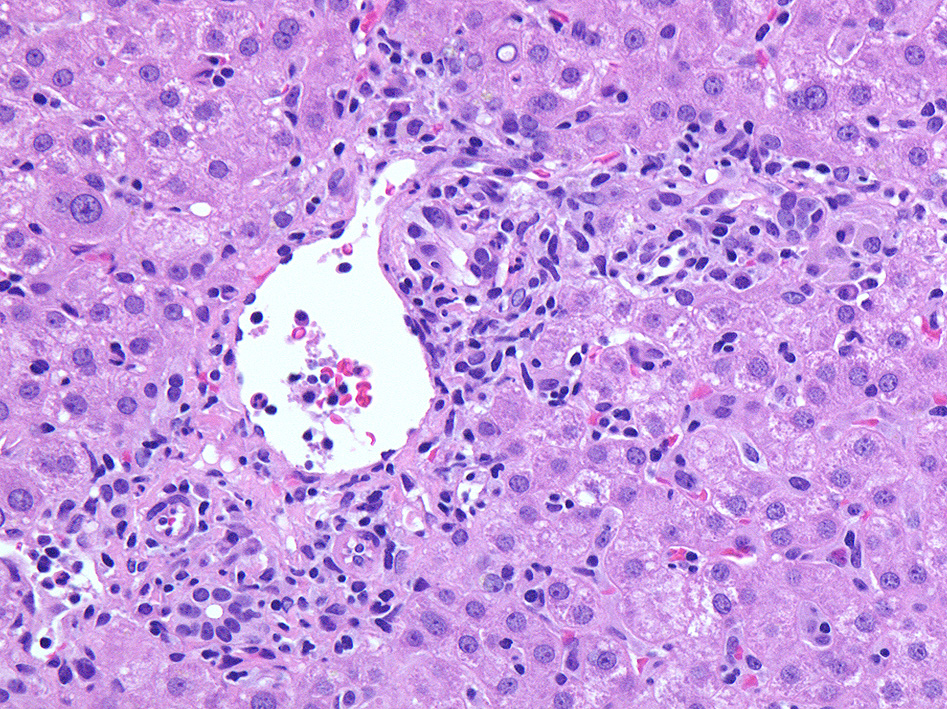

肝臓針生検組織 Virtual Slide--->肝針生検 右クリックで新しいウィンドウ/タブで開くとべんりです。

グリソン鞘, 小葉にリンパ球の浸潤がめだつ。

免疫染色

浸潤リンパ球はCD3+, EBER-ISH+. CD20+細胞はごく少数. CD56, granzymeB陽性リンパ球はほとんど認められない。